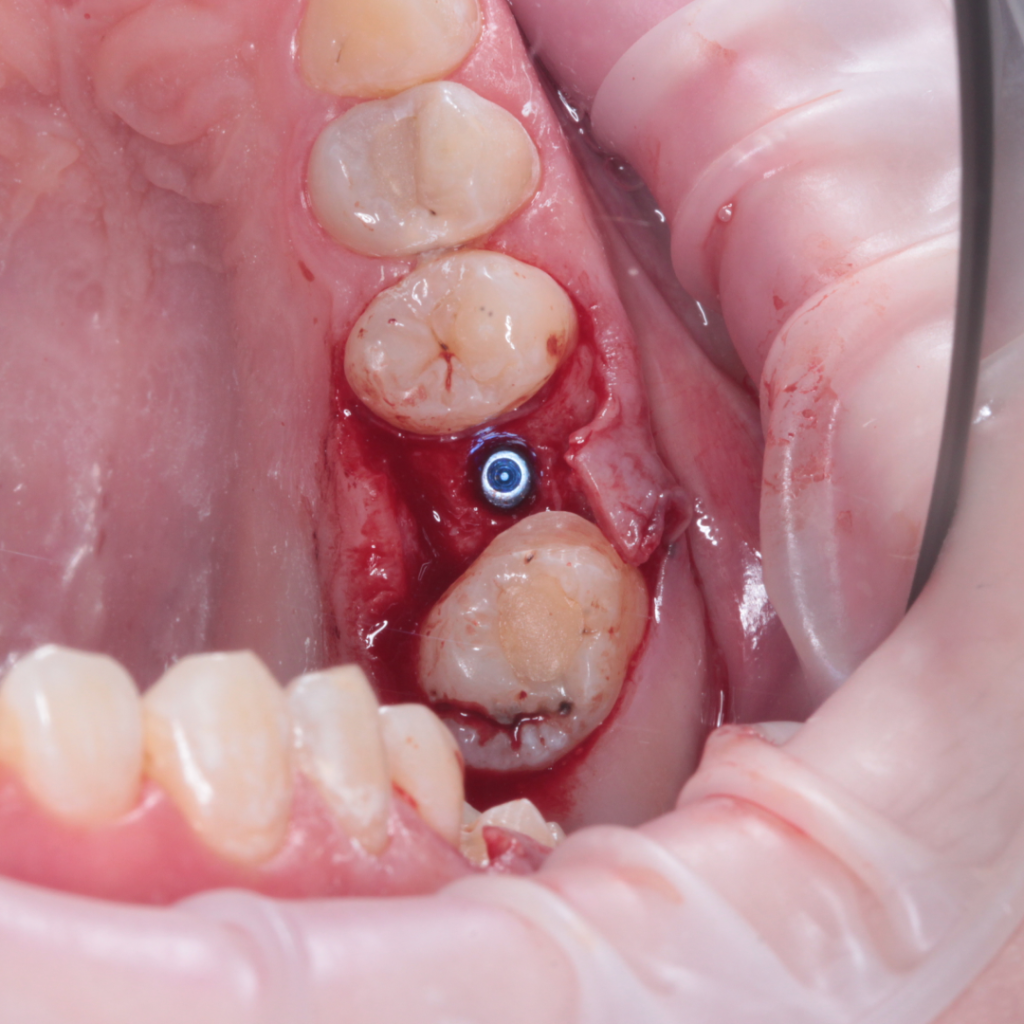

- Поднятие дна верхнечелюстной пазухи

- Установка имплантата AnyRidge

- Забор крови и центрифугирование фибриновых сгустков PRF

- Укладка фибриновых сгустков APRF под слизистую оболочку верхнечелюстной пазухи

- Наложение швов